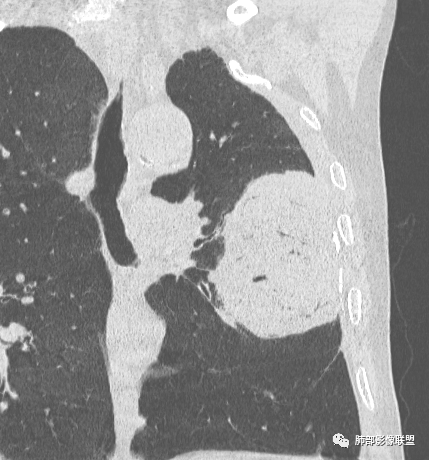

左肺上叶大肿块,膨胀性生长,边界清,密度较低,见部分坏死区,强化弱,肿块见支气管充气V扩张征,分布僵直,枯树枝特点,另一个重要特点血管造影征,淋巴瘤,肿块长轴与胸膜平行,与隐球菌鉴别,隐球荚膜抗原检查,明确诊断经皮肺穿刺。另胸膜钙化(问诊既往有无患胸膜炎病史)。

如果粘液腺Ca,周边太干净了,不支持。

老年男性,糖尿病病史,消瘦、乏力三个月,影像表现左肺上叶胸膜下团块,有一定张力,内部疏松,可见支气管影及坏死区,增强病灶边缘环形强化,内部未见强化,考虑炎性肉芽肿病变,隐球?奴卡?放线菌?鉴别淋巴瘤。

左肺上叶胸膜下肿块,宽基底与胸膜相连,跨叶裂,边缘清晰膨隆,其内支气管充气,部分扩张、僵直,无明显强化,血管造影征,考虑淋巴瘤,鉴别腺癌

左肺胸膜下巨大占位,跨叶裂,宽基底与胸膜相连,胸膜钙化,平扫密度较低,强化不明显,可见内部血管显影,支气管充气征和扩张,考虑为恶性,倾向于淋巴瘤

左侧胸腔巨大肿块,跨叶生长,临近胸膜钙化,边缘模糊,可见支气管影,定位肺内,增强后轻度强化,边缘见血管影,考虑淋巴瘤,鉴别肉瘤

老年,明显消瘦,左侧胸廓轻度缩小?胸膜增厚,见钙化,以前结核?接触其他?整个肿块膨隆,坏死不明显,支气管通畅,轻度扩张轻度强化,考虑恶性,淋巴瘤可能

左肺上叶胸膜下肿块,膨胀性生长,边界清晰,密度不均部分坏死,未见强化,病灶内支气管迂曲扩张,病灶长轴与胸膜平行,胸膜下脂肪间隙存在,胸膜钙化,考虑放线菌?毛霉?鉴别淋巴瘤

支持淋巴瘤,左上肺大肿块,有分叶,边缘光整,病灶内密度不均,可见支气管扩张征,增强后可见血管影征。周围肺野清晰。

左肺上叶肿块,宽基底与胸膜相连,跨叶裂,边缘清晰膨隆,可见小分叶,其内支气管充气,部分扩张、僵直,呈枯枝征,支气管达边征,增强无明显强化,可见血管造影征,考虑恶性病变,淋巴瘤,鉴别粘液腺癌。

大肿块,边缘光滑,深分叶

近端支气管堵塞、推移为主

部分类似于脐凹征

内部支气管扩张

肺动脉推移为主,边缘部分进入

1)部位:周围型或中央型软组织肿块,以周围型为多见,且肿瘤多位于肺上叶。如本例:该肿瘤位于左肺上叶。

2)大小及形态:由于本病恶性程度高,早期症状不明显,发现时肿块均较大。如本例病变巨大。

3)肿块边界和边缘:多较清楚,呈圆形、类圆形,且由于肿块生长速度不均匀,可见分叶,毛刺少见。有报道肿块周围毛玻璃影是多形性癌特征表现。

4)密度:肿块平扫为软组织密度,由于体积较大,内部常见大片状坏死,可出现不规则厚壁空洞或坏死内多发无壁小空洞,坏死多不均匀:坏死灶内可见如柳絮样的斑片样强化灶,坏死边缘与非坏死区分界不清本例坏死较明显,密度不均匀。